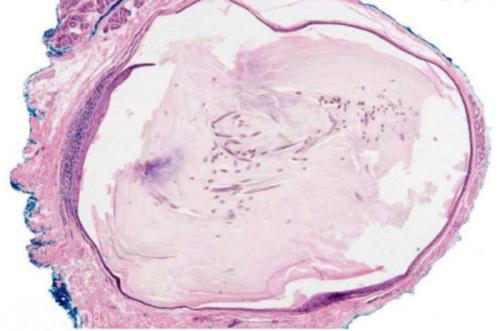

皮樣囊腫或表皮樣囊腫為胚胎發(fā)育時(shí)期遺留于組織中的上皮發(fā)展形成的囊腫:后者也可由于損傷、手術(shù)使上皮細(xì)胞植入而形成,皮樣囊腫囊壁較厚,有皮膚及皮膚附件(如汗腺、毛囊等)組成,囊腔內(nèi)有脫落的上皮細(xì)胞、皮脂腺、汗腺和毛發(fā)等結(jié)構(gòu)。